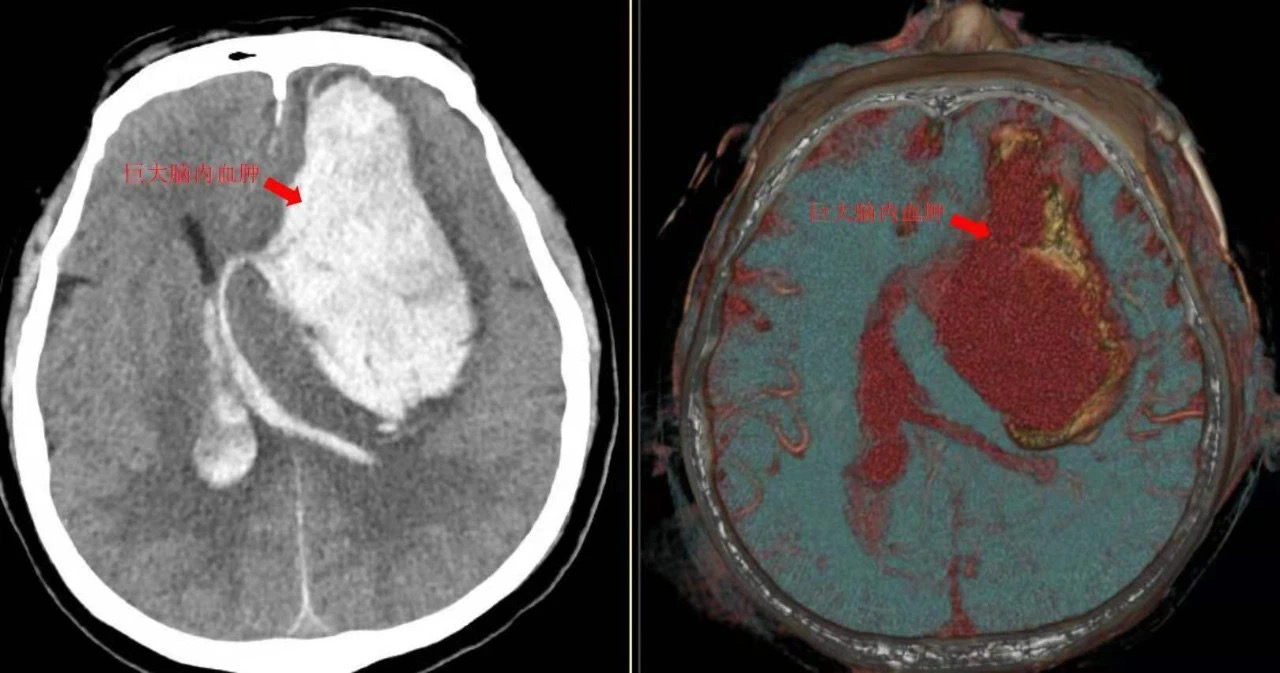

神经内科急诊值班医师王也接诊时发现刘先生双侧瞳孔已有散大的迹象,随后CT影像显示脑部大量出血。为了找出病因,王也紧急安排了CT血管造影检查(简称CTA),确诊“病根”——脑动脉瘤破裂。

“手术结束后,大夫告诉我老刘散大的瞳孔已恢复正常,那一刻我揪着的心也才跟着恢复了正常。”妻子激动地说道,“后来我们家属把出事当天和术后的片子给国内不同医院的医生看,他们说这样大的出血量能抢救回生命实属不易,远在美国的医生看完片子也说‘This looks like an in tracerebral hematoma with a good evacuation of blood(这看起来像是颅内血肿,血液清除良好)’。”